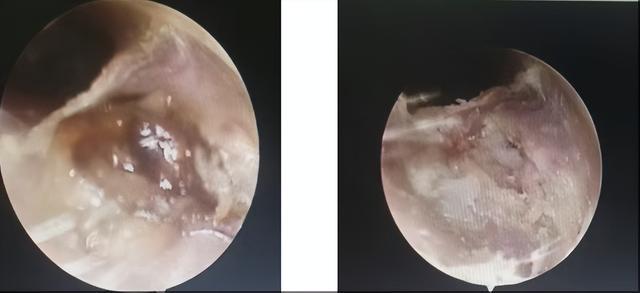

经过充分的沟通并在排除手术禁忌症后,医生在全麻下为燕大伯实施了耳内镜持续灌流模式下行左侧外耳道病损切除术+左侧耳道成型术+游离皮片取皮术+耳道植皮术,手术顺利,麻醉满意。

术后常规治疗后顺利出院,病检结果提示:符合外耳道胆脂瘤。

(▲术后三周复查耳内镜)

近日燕大伯复查显示创面恢复良好,同时术后左耳疼痛症状也已消失。